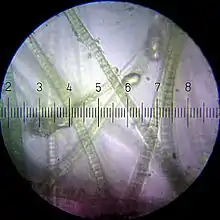

Axonal transport is essential to neuron cell growth and survival. Axon of neuron is 1,000 or 10,000 times the length of the cell body, but contains no ribosomes, which means that it is unable to produce protein. All proteins and membrane must synthesize proteins in neuronal cell body or neuron cell dendrite, and then transport back to the axon. The motor protein kinesin is a motor protein used during anterograde processes while dynein is used in retrograde processes .

Vesicular cargoes move 50-400 mm/day whereas proteins move less than 8 mm/day.